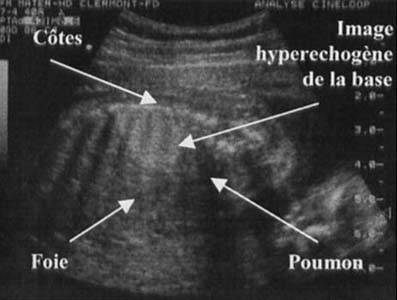

Masse hyperéchogène dans le base pulmonaire